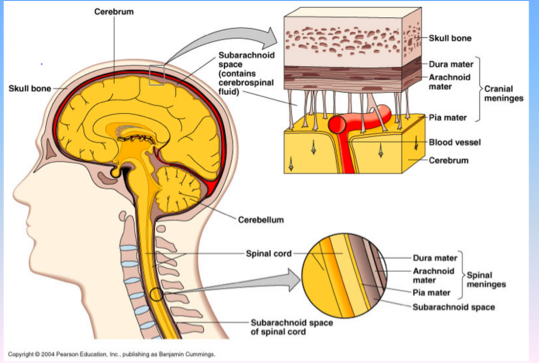

- What is a subarachnoid hemorrhage?

- Where is it at?

- What is a subdural hematoma and where is it at?

- What is an epidural hematoma and where is it at?

- WHat is a epidural hematoma associated with?

Subarachnoid hemorrhage (see picture-layered out on the surface of the brain)

- Arterial bleeding on the surface of the brain

- Between the pia mater and the arachnoid mater

Subdural hematoma

- Venous bleeding between the arachnoid and the dura mater

Epidural hematoma

- Dural artery or venous sinus bleeding between the skull and dura

- Associated with skull fracture

Describe the following for Epidural, Subdural and Subarachnoid:

- In relation to the dura

Epidural

- Above the dura

Subdural

- Below the dura

Subarachnoid

- Below the arachnoid